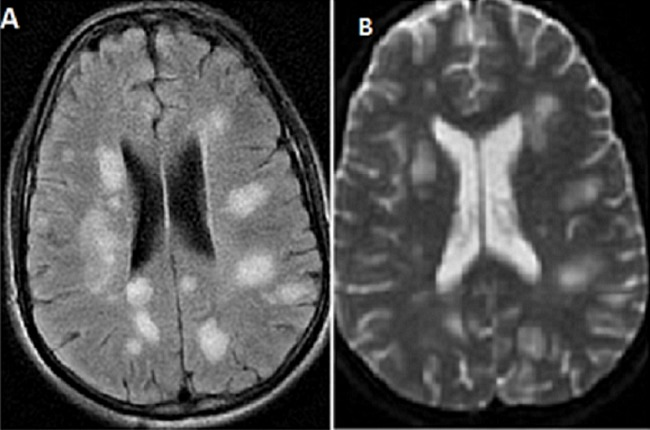

Typical MRI findings in #ADEM: A) Multifocal, bilateral, asymmetric white matter lesions on #FLAIR. B) Hyperintense lesions on #T2 sequences, consistent with CNS inflammation. Additional findings: Rare T1 hypointense lesions and deep grey matter involvement (e.g., thalamus or

Typical MRI findings in #ADEM: A) Multifocal, bilateral, asymmetric white matter lesions on #FLAIR. B) Hyperintense lesions on #T2 sequences, consistent with CNS inflammation.

Additional findings: Rare T1 hypointense lesions and deep grey matter involvement (e.g., thalamus or